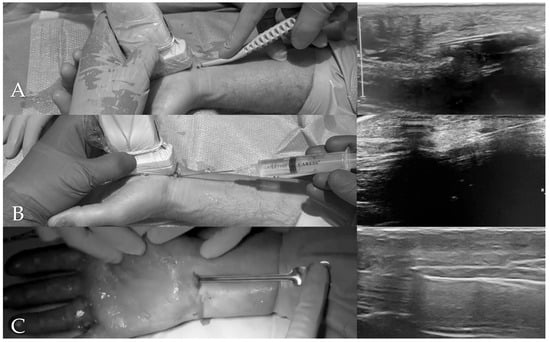

The procedures were performed using three ultrasound-guided techniques (Figure 1): (1) a method employing the single-use Kemis® H3 knife (Newclip Technics, Nantes, France); (2) the percutaneous needle release technique described by McShane et al. [7]; and (3) the technique introduced by Dr. Brando and presented at the 2023 Congress of the Italian Society for Surgery of the Hand (SICM). Sterile draping consisted of a two-component system: a small drape placed between the arm table and the hand, and a large fenestrated drape secured to the forearm with adhesive to separate the surgical field from the patient.

In the Kemis® H3 knife technique, after identifying on ultrasound the median nerve, ulnar artery, and the distal landmarks of the transverse carpal ligament (TCL), a small incision was made proximal to the wrist crease. A mosquito forceps was first introduced above and below the TCL to define the plane, and the Kemis® H3 was then advanced under continuous ultrasound guidance, ensuring that the blade encompassed the entire ligament. The TCL was divided from proximal to distal, using Doppler to avoid vascular injury, and completeness of the release was confirmed on ultrasound.

In the McShane percutaneous needle release technique, through a single entry point at the proximal wrist crease, an 18-gauge spinal needle was introduced under continuous ultrasound control. The needle was advanced parallel to the median nerve, kept superficial and slightly ulnar to it, and repeatedly passed through the TCL to fenestrate the structure until the needle could pass freely, while carefully avoiding nerve and vascular injury.

In the Brando technique, a transverse entry point just ulnar to the palmaris longus tendon at the proximal wrist crease was used to access the carpal tunnel within the ultrasound-defined safe zone. A button-tipped probe was advanced beneath the TCL, confirming that it lay ulnar to the median nerve and superficial to the flexor tendons, and excluding superficial palmar arch involvement on power Doppler. A grooved director (slotted guide) was then advanced over the probe; the probe was removed, and a round-tipped microblade, oriented upward, was introduced. Advancing the blade from proximal to distal along the guide completed the release of the TCL, which was confirmed by supraretinacular migration of the guide.

Despite the technical differences, all approaches share the same principles: continuous ultrasound visualization to protect adjacent structures and confirmation of complete TCL release.

Figure 1. Representative images of three ultrasound-guided techniques for carpal tunnel release. (A) Kemis® H3 knife; (B) McShane needle release; (C) Brando technique. Left panels show the instrument approach; right panels show real-time ultrasound visualization.